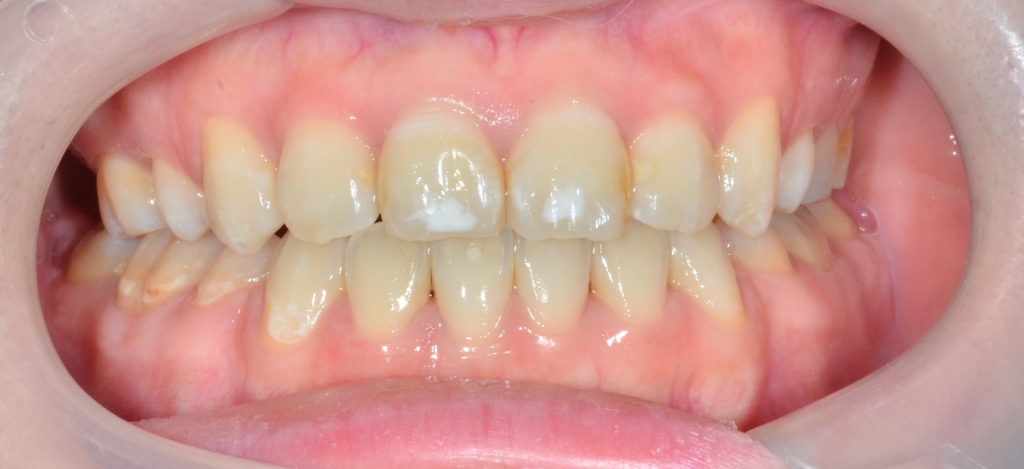

【After】

歯並びがキレイになったことはもちろん、口元や横顔もとてもスッキリさせることができました。

治療前後のお顔の写真を見てもらえれば、その変化が良く分かると思います。

治療前は明らかに飛び出ていた口元が、治療後は十分に引っ込み、しっかりEラインに収まってスッキリしています。

口元の変化がハッキリと分かります

口元が飛び出た感じも無くなりました

色々ありましたし、頑張ってももらいましたが、患者さんにもとても満足してもらえました ♪